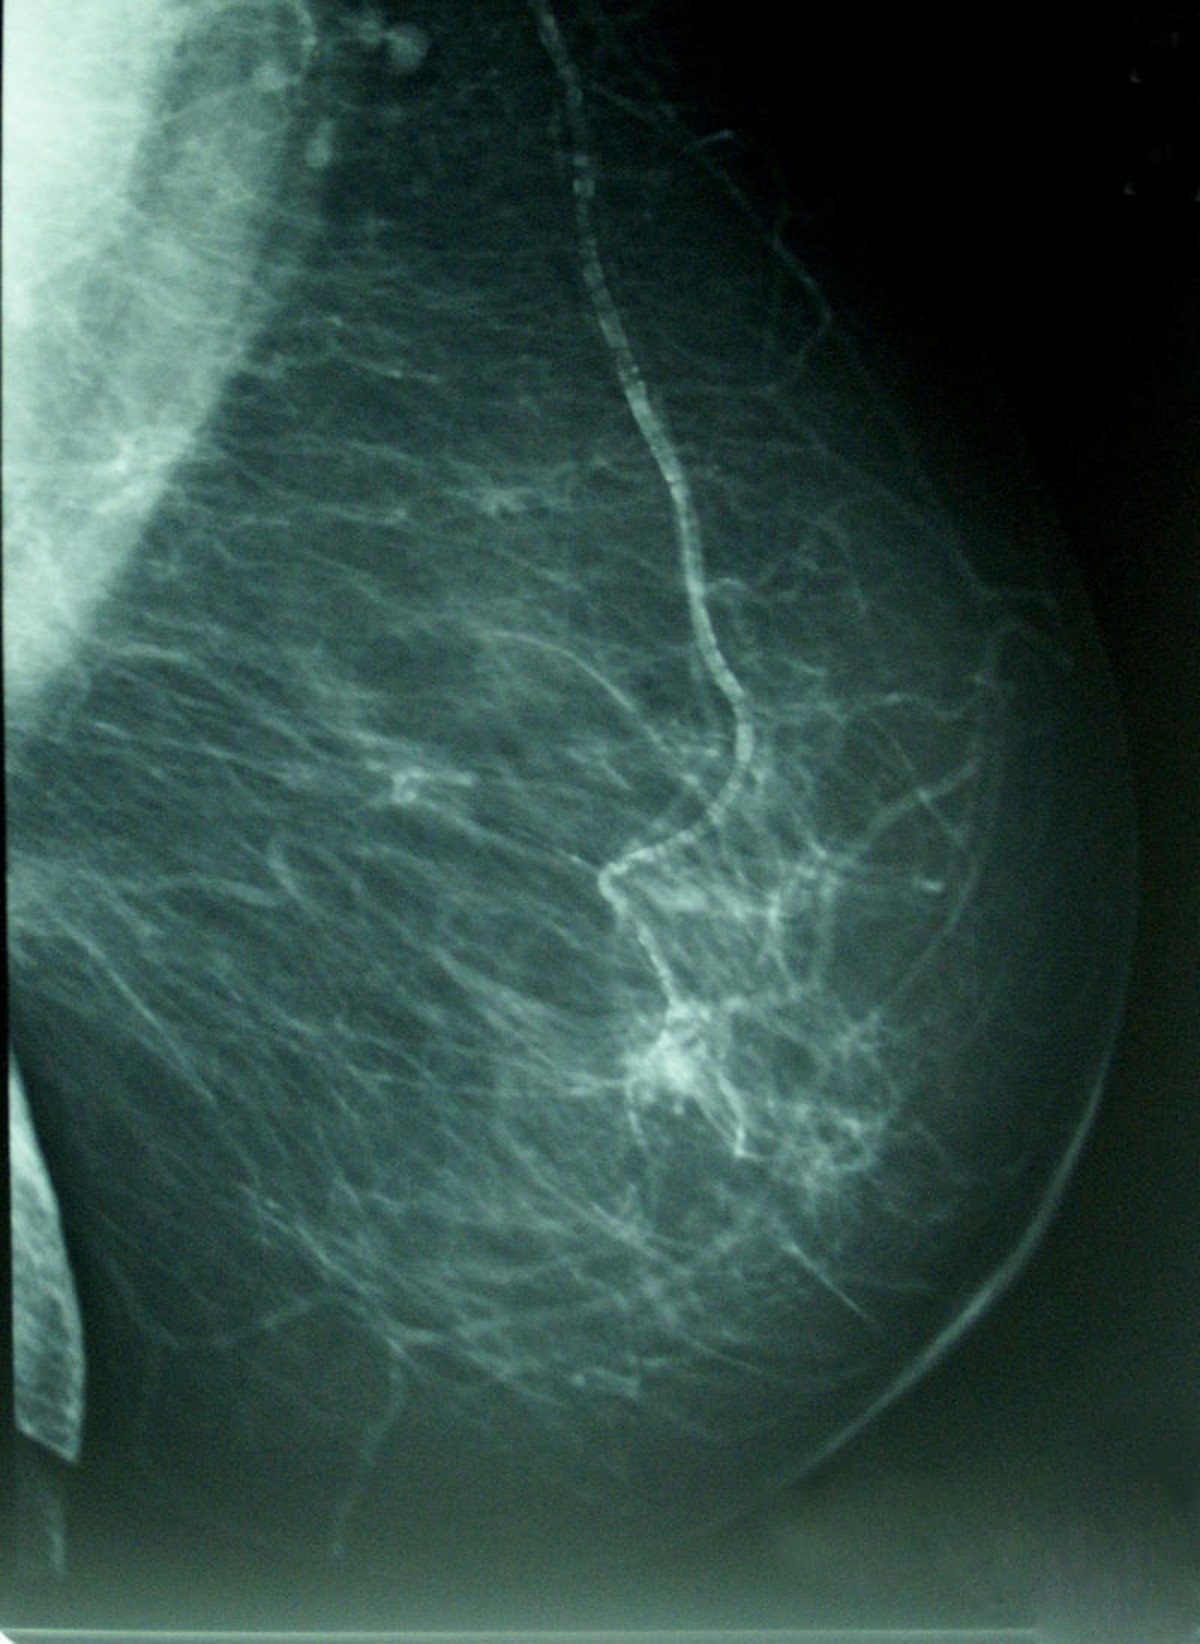

Cáncer De Mama, Densidad Mamográfica

Foto: WIKIPEDIA/A. AVENDAÑO

Además, existe un programa poblacional de detección precoz del cáncer de mama por la vía de mamografía, que funciona desde el año 1997. Durante el último año se ha ampliado la edad de cobertura, de manera que actualmente se puede beneficiar a las mujeres de entre 50 y 69 años.